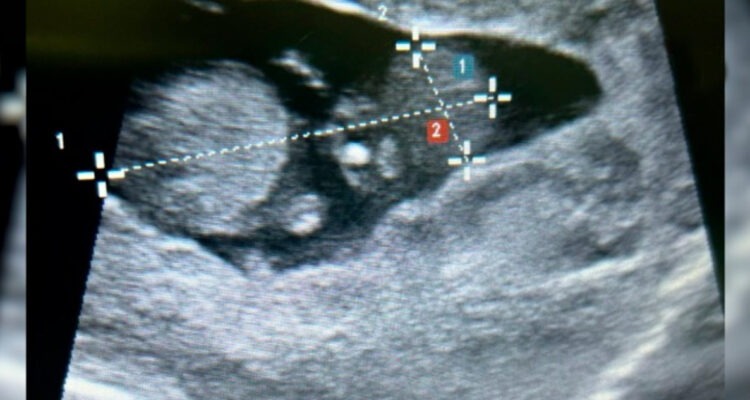

Relató que le hicieron una ecografía en el Hospital Carlos Lanfranco La Hoz, en Puente Piedra, pero que los especialistas que la atendieron nunca le dijeron que tenía un embarazo complicado. Si bien había vivido una experiencia de embarazo, en esta segunda oportunidad tuvo síntomas extraños en los últimos meses, pero igual no los relacionó a peligro con su salud y la de su bebé.

El 20 de noviembre, Valeria empezó el trabajo de parto y acompañada de su esposo, Jorge Veliz, se dirigieron al Hospital Carlos Lanfranco La Hoz. Debido a que no dilataba bien, los especialistas decidieron hacerle una cesárea. Los médicos se quedaron asombrados en la cirugía al encontrar a la bebé dentro de la placenta adherida al hígado y en otros órganos y que no se había implantado en la cavidad uterina lo que ellos llamaron un milagro de vida.

Los profesionales de la salud retiraron con sumo cuidado a la bebé, de nombre Ayleen, que nació con 3 kilos 600 gramos de peso. Ella estaba saludable y todo este tiempo se había alimentado a través de las arterias del hígado.

EMBARAZO ECTÓPICO ABDOMINAL. Un embarazo ectópico es cuando el embrión no se desarrolla en la cavidad uterina. El 96 % de los embarazos ectópicos, fuera del útero, se dan en la trompa de Falopio y un 4 % en la zona abdominal. En este caso, y lo que lo hace especial, es que el óvulo fecundado se implantó en el hígado y a través de las arterias de este órgano el feto se iba alimentando.